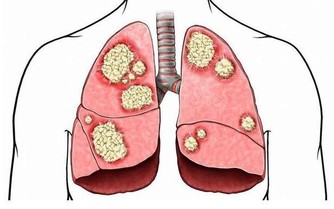

8 、咳嗽不止。

美國喬治城大學醫學院拉尼特·米歇里博士表示,

如果莫名其妙的咳嗽持續不斷,超過3—4周,就應該及時看醫生,有可能是肺癌或喉癌的徵兆。